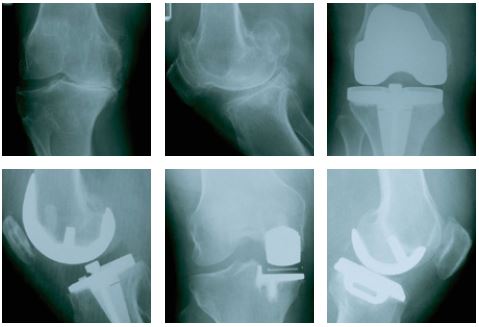

L'arthroplastie du genou est réalisée sous anesthésie. Il y a plusieurs types d'anesthésie disponibles. L'anesthésiste vous expliquera, avant l'intervention, les différentes options qui peuvent être envisagées dans votre cas particulier. L'arthroplastie totale du genou peut être une intervention extrêmement efficace. Lors de l'intervention, le chirurgien n'enlève pas la totalité du genou. En fait, il remplace uniquement les parties cartilagineuses endommagées de l'articulation, recréant ainsi la surface de glissement douce qui avait été abîmée par l'arthrose.

Pour accéder à l'articulation, une incision est pratiquée sur la face antérieure de votre genou. Les extrémités osseuses endommagées sont remplacées par des composants qui reproduisent les surfaces lisses du cartilage et permettent de recréer les formes naturelles d'un genou sain. Le métal (acier inoxydable ou titane) et le polyéthylène (plastique) utilisés permettent aux implants de glisser entre eux de manière douce et harmonieuse comme le cartilage naturel.

La mise en place d'une prothèse de genou unicompartimentale est indiquée dans les cas d'arthrose localisée au compartiment fémorotibial interne. La technique utilisée est très peu invasive et permet de restaurer la cinétique originelle du genou. La durée moyenne de l'intervention est une heure et demie. Les soins préopératoires ainsi que le temps passé en salle de réveil peuvent être évalués à 2 - 3 heures.